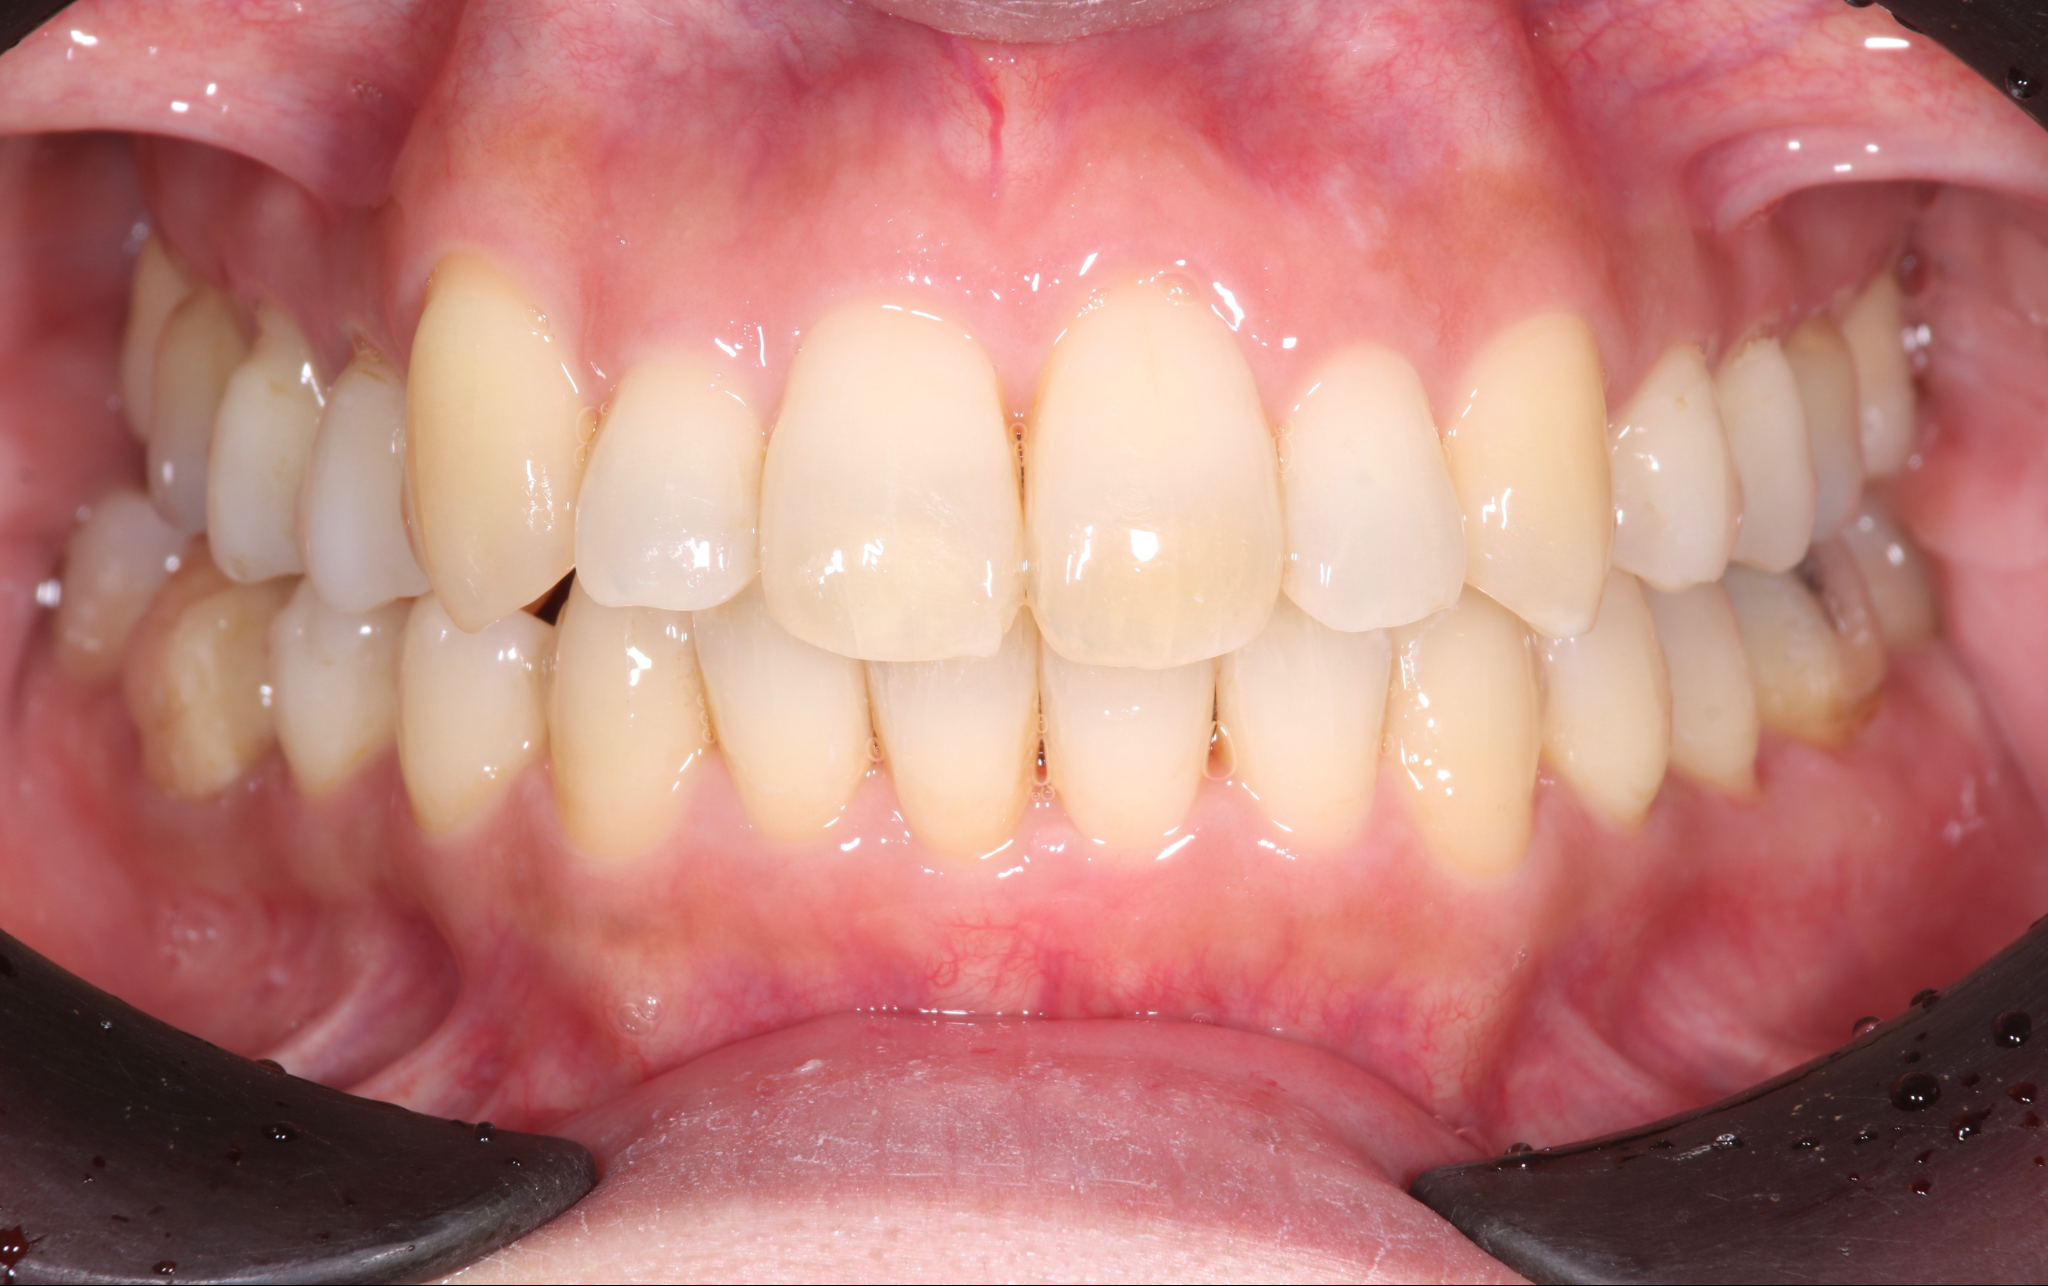

術後の状態

治療概要

| 患者さんの状態 | 重度の叢生 |

|---|---|

| 治療内容 | MEAWを用いた矯正治療(非抜歯) |

| 治療期間 | 約2.5年 |

| 治療費用 | 1,320,000円(税込) ※矯正治療費のみです。 |

| 治療のリスク | 歯肉退縮、自由診療、後戻り、口腔内清掃が難しい |